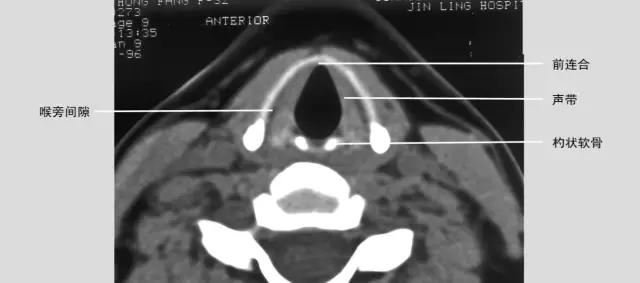

正常喉部CT